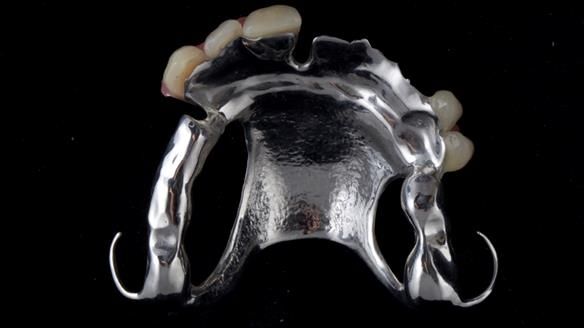

Welcome to Newsletter 67, where I will detail the making and fitting of an upper metal-based partial denture/splint (“Combat denture”) for Brian, a patient with a powerful locked occlusion and deep overbite. The full protocol workflow is presented here.

- Bruxism: The upper and lower teeth are worn and chipped due to heavy clenching and grinding. With a powerful bite and limited space for replacement teeth, dental implants supported fixed teeth are not recommended. A simpler solution is a metal-based partial denture/splint (“Combat denture”) as planned below. This will act as a splint to protect and replace the missing teeth.

Treatment Process: I provided the clinical work, while Rowan Garstang handled the technical work. The treatment required five visits to fit the RPD. The worn lower anterior teeth were then built up. Unfortunately, I did not check the guidance on the denture teeth after this, and tooth 11 fractured off the denture. Brian was very understanding, and I adjusted the denture thoroughly. It has been fracture-resistant and trouble-free for the last three years.